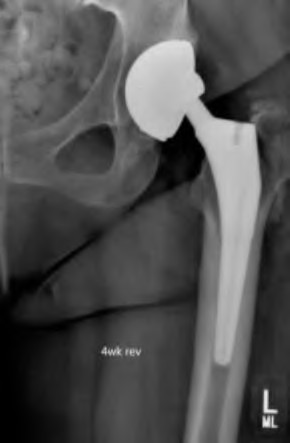

A 72-year-old female falls and sustains a periprosthetic femur fracture around her cementless total hip arthroplasty. Radiographs reveal a fracture extending just distal to the tip of the stem. The stem is radiographically loose, but there is excellent proximal and distal bone stock. According to the Vancouver classification, what is the fracture type and the recommended surgical treatment?

Explanation